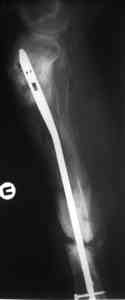

Пример (пациент 46 лет, лечился у нас 4 года назад, внутренний остеосинтез выполнен с определенными погрешностями, но перелом сросся и рецидива инфекции не было): рис. 1,2 - при переводе к нам в институт, рис. 3 - после микрохирругической пластики, рис. 4, 5 - после интрамедуллярного остеосинтеза, рис. 6, 7, 8 - внешний вид и рентгенограммы после окончания лечения